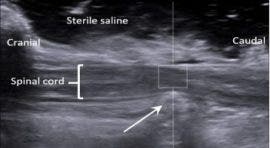

In connection with this research, the neurology team at Highcroft is undertaking another research project (led by Drs Jon Prager and Nicolas Granger) with the objective to measure swelling of the spinal cord during surgery. This is possible using the ultrasound machine at Highcroft Veterinary referrals, which is equipped with specific software that can measure how quickly sound waves propagate within tissue, a technique called ‘elastography’. In essence, ultrasound elastography gives a reading of the ‘stiffness’ or ‘elasticity’ of tissue. Due to the delicate nature of the spinal cord, it is suggested that its structure, and therefore its elasticity, changes after injury. In a set of preliminary data we have collected, it appears that how much the spinal cord elasticity changes after injury is related to the clinical severity of injury, and we are proposing to continue to describe these changes. In time, this novel measure may allow more accurate prognosis for dogs that have spinal cord injury.